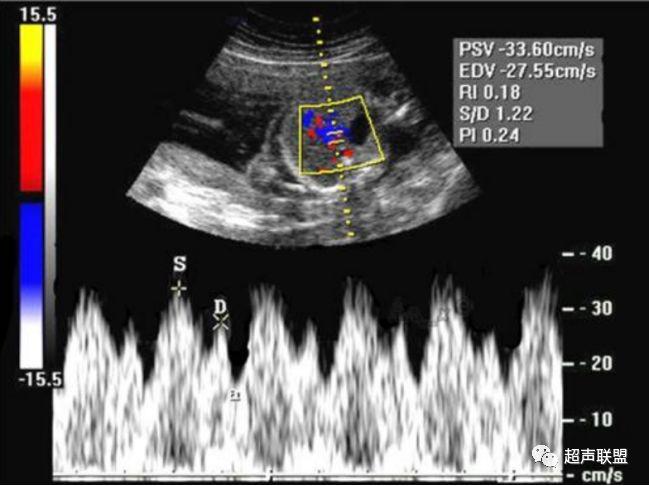

2 胎儿大脑中动脉测定

缺氧早期大脑血液供应增加,颅内血管扩张,阻力降低,舒张末期血流速度增加,PI、RI值下降,说明缺氧早期的血流再分配。当大脑中动脉RI、PI值明显下降,而脐动脉和腹主动脉的PI值升高,大脑中动脉PI值与脐动脉PI值的比值低于2个标准差时,提示严重缺氧的存在。

1、比值标准:大脑中动脉阻力降低,妊娠期,大脑中动脉RI <脐动脉RI;

4、当大脑中动脉RI及PI值明显下降,而脐动脉及腹主动脉的PI值之间升高,大脑中动脉PI值与脐动脉PI值低于两个标准差时,提示为胎儿严重缺氧;

图3 正常大脑中动脉血流频谱

图4 大脑中动脉血流阻力减低